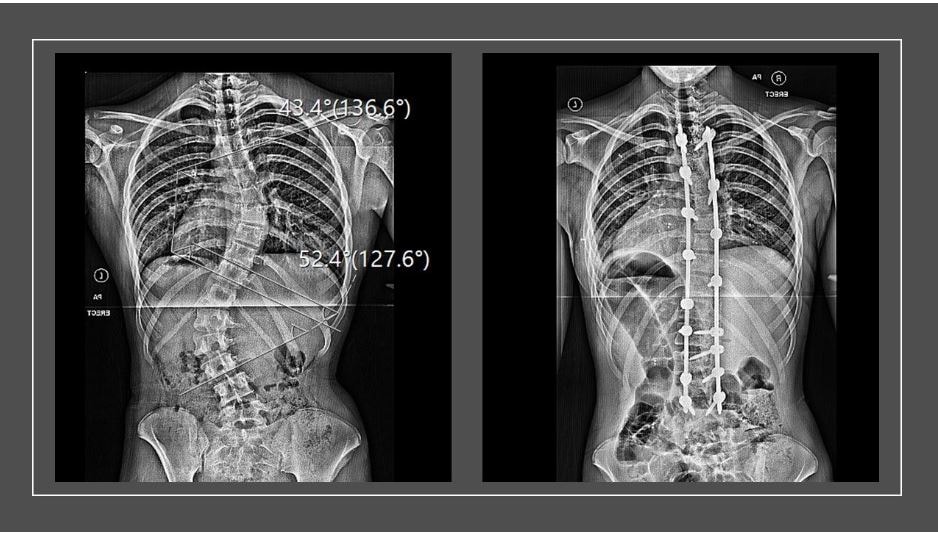

Paramedic Practice

Paramedic Science